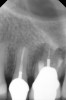

Clinical procedure: Once a perforation occurs, the extent of the perforation must be assessed. If there is an adjacent bony defect, the bony defect should first be filled with an osteoconductive or osteoinductive material. This can be done with a bone graft, calcium sulfate, or collagen/gelatin sponge. The dentinal portion of the tooth that has been perforated is then restored with MTA (Figure 9 through Figure 14).

Fig 9 Preoperative radiographs showing mesial perforation.

Figure 9

Fig 10. Preoperative radiographs showing mesial perforation.

Figure 10